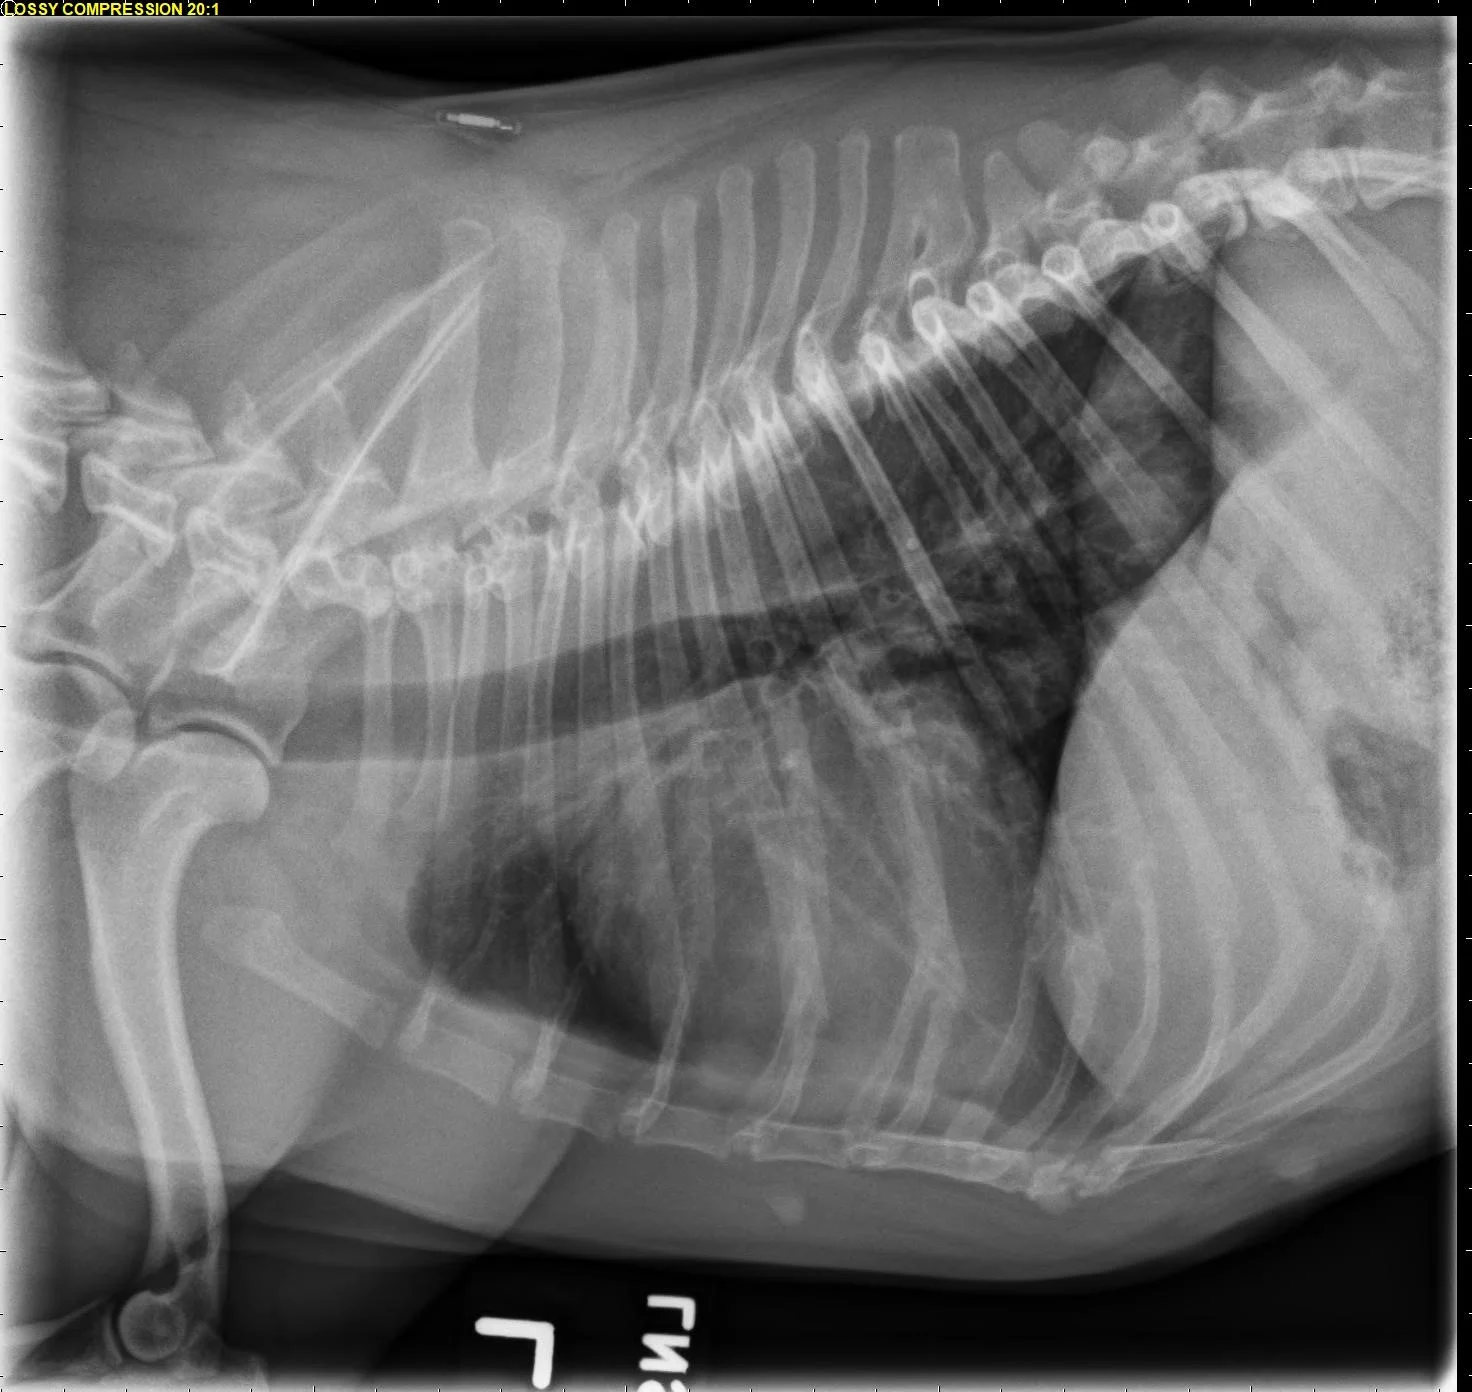

Common congenital heart diseases in dogs include pulmonic stenosis, patent ductus arteriosus, and subaortic stenosis. In addition to providing valuable information regarding the pulmonary parenchyma and vasculature, thoracic radiography may provide clues into which type of congenital heart disease is present. For example, a dog with left-sided cardiomegaly and a bulge in the ascending aorta raises suspicion for subaortic stenosis (Figure 10), whereas a dog with right-sided cardiomegaly without an MPA bulge raises suspicion for tricuspid valve dysplasia (Figure 11). Qualitative assessment of individual cardiac chambers with thoracic radiography can be an inaccurate method for diagnosis of congenital heart disease and right-sided heart enlargement in dogs. Definitive diagnosis is achieved with echocardiography.17,18 An objective parameter (ie, vertebral right heart index [VRHi]) could be a useful tool for accurate radiographic determination of right-sided cardiomegaly, although studies are needed to evaluate the influence of left-sided heart enlargement and individual breed differences in the normal range, as well as breed-specific cutoffs used for this parameter (Figure 12).19

FIGURE 11 Right lateral (left) and VD (right) projections of a crossbreed dog with tricuspid valve dysplasia. The cardiac silhouette has increased width, and the regions of the right atrium and ventricle show roundness. The cardiac apex is displaced to the left secondary to right-sided enlargement (right). The caudal vena cava (arrowheads) is dilated, and there is loss of abdominal serosal detail secondary to increased systemic venous pressures and right-sided CHF, respectively. The pulmonary vasculature is small secondary to pulmonary hypoperfusion (given significant regurgitation across the tricuspid valve and decreased forward blood flow). VHS, VLAS, M-VLAS, and VRHi collected from the right lateral view are 12.3, 2.3, 2.7, and 3.8, respectively. Images courtesy of Bruna Del Nero, DACVIM (Cardiology)